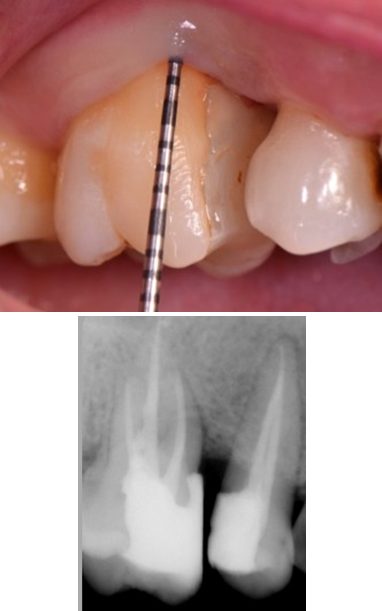

A 22-year old female patient presented in our private dental practice set up with complaint of pain, food stagnation, foul smell and loosening of couple of teeth in upper jaw. Intraoral examination revealed vertical bone loss around distal surface of upper right second premolar and mesial surface of first molar (Figure 1). The pocket depth was measured to be more than 15mm (Figure 2). The severely affected premolar and molar, on pulp testing showed pulpal involvement leading to diagnosis of endo-periodontal lesion.

After 4 weeks, surgical intervention was carried out. Under local anesthesia a full thickness mucoperiosteal flap was reflected to entirely expose the underlying bony defect (Figure 3). Scaling and root planing was again carried out with osteoplasty to make sure the site becomes clean and non-infected. Freeze-dried bone allograft (surreoss) 0.5cc powder was condensed into the bone defect (Figure 4) and 1x2cm Acellular Dermal Matrix Membrane (Surederm) was placed over the graft area to prevent the epithelial cell migration (Figure 5). Finally, interrupted silk (4/0) suture were placed to approximate the soft tissue (Figure 6). Post-operative instructions were given and patient was directed to use chlorhexidine gel and rinse three times for a period of 15 days and suitable antibiotics were prescribed for five days. As the prognosis of tooth was highly questionable patient was recalled on follow up after 1 week, 2 weeks and 4 weeks. After 3-months’ patient’s intraoral radiograph showed remarkable improvement in regard to bone repair and patient’s satisfaction (Figure 7). Clinical evaluation on 3-month, 2-year and 5-year recall exhibited marked reduction in pocket depth up to 12mm with radiographic evidence of further hard tissue repair (Figure 8). A 5-year recall showed a stable probing depth of 3 mm with functionally standing in her oral cavity despite the fact that she refused to have a crown on the treated tooth (Figure 9).